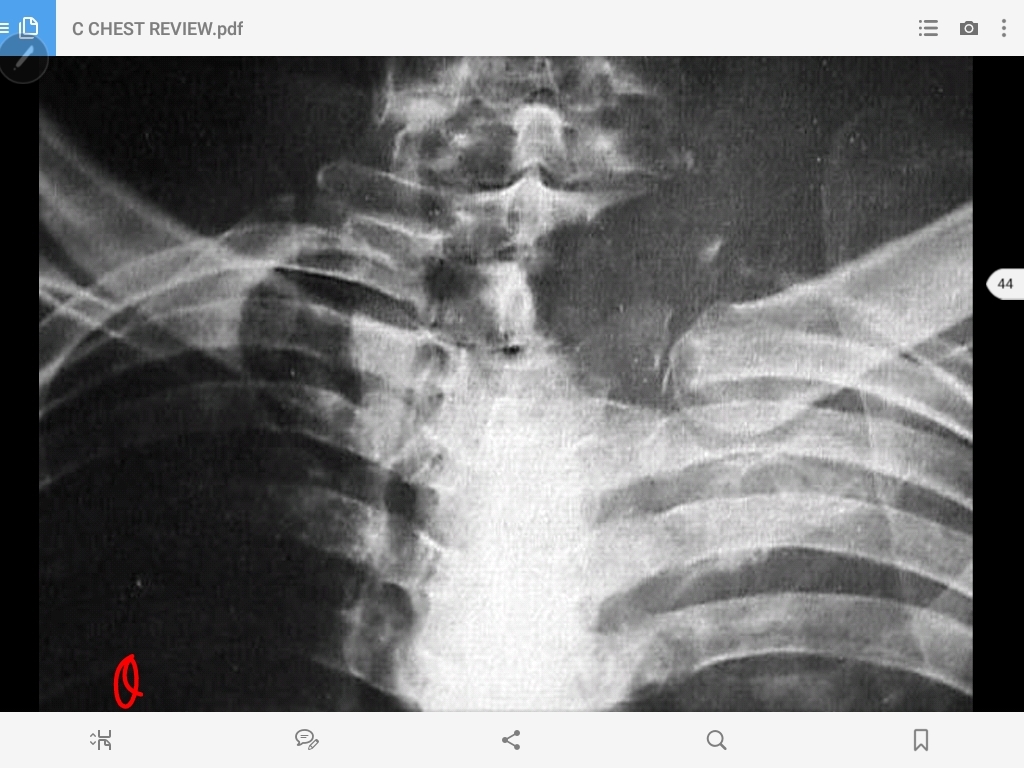

pancoast tumor